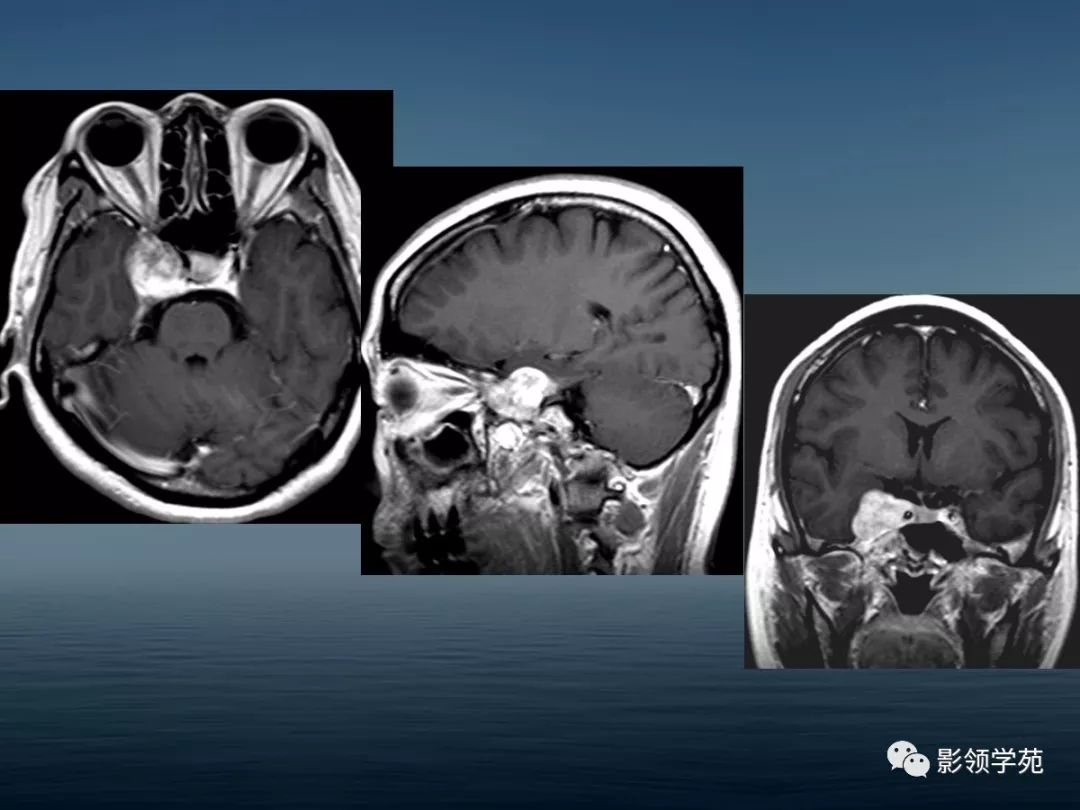

鞍区病变的ctmri诊断